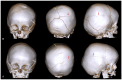

Craniosynostoses (CRS) are caused by the premature fusion of one or more cranial sutures, with isolated nonsyndromic CRS accounting for most of the clinical manifestations. Such premature suture fusion impacts both skull and brain morphology and involves regions far beyond the immediate area of fusion. The combined use of different neuroimaging tools allows for an accurate depiction of the most prominent clinical-radiological features in nonsyndromic CRS but can also contribute to a deeper investigation of more subtle alterations in the underlying nervous tissue organization that may impact normal brain development. This review paper aims to provide a comprehensive framework for a better understanding of the present and future potential applications of neuroimaging techniques for evaluating nonsyndromic CRS, highlighting strategies for optimizing their use in clinical practice and offering an overview of the most relevant technological advancements in terms of diagnostic performance, radiation exposure, and cost-effectiveness.